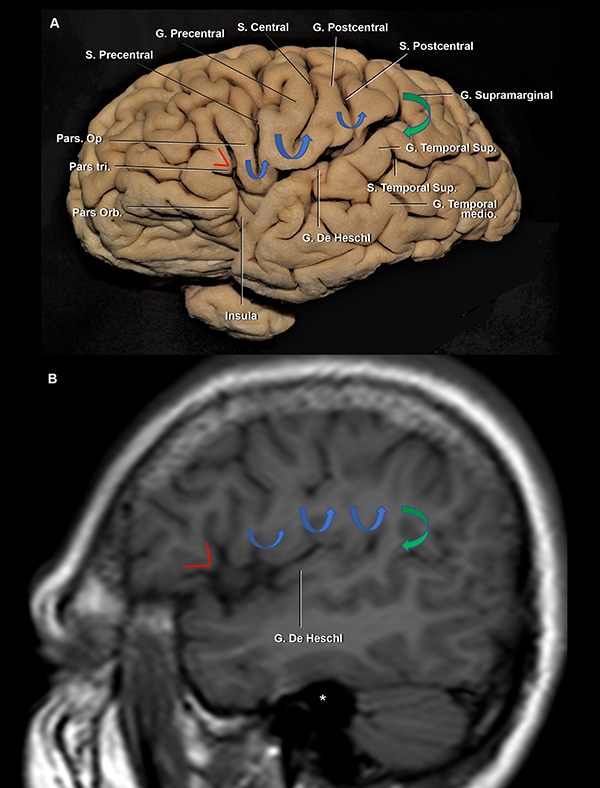

Figura 5: A. Vista lateral de un hemisferio cerebral izquierdo. B. RMN, secuencia T1, corte sagital. La pars triangularis tiene forma de “V” (líneas rojas). Luego, encontramos 3 giro con forma de “U” (flechas azules), de anterior a posterior: 1) pars opercularis; 2) giro subcentral; y 3) la conexión entre los giros postcentral y supramarginal. Finalmente, la flecha verde marca la conexión con forma de “C” entre los giros supramarginal y temporal superior. Se observa al giro de Heschl enfrentado al postcentral. Ambos se encuentran en el mismo plano coronal que el CAE. Asterisco: proyección medial del CAE. S: surco; G: giro; Sup: superior; inf: inferior.

Figura 3: Vista lateral de un hemisferio cerebral derecho. Estrella azul: punto silviano anterior. El limen insular, el genu de la ACM y, frecuentemente, la bifurcación de la ACM se localiza medial e inmediatamente anterior a este punto. Estrella naranja: punto rolándico inferior. Estrella roja: punto silviano posterior. La ínsula se proyecta lateralmente desde el ramo horizontal a la parte más anterior del giro supramarginal; y desde la parte más superior de la pars triangularis y el ramo ascendente hasta el surco temporal superior. Línea punteada verde, azul y roja: proyección de los surcos semicirculares insulares anterior, superior e inferior, respectivamente. S: surco; G: giro; Ram: ramo; Sup: superior; Med: medio; Asc: ascendente; Desc: descendente; Term: terminal; Orb: orbitalis, Tri: triangularis; Op: opercularis; Hor: horizontal.

El tronco silviano se extiende hasta la punta inferior de la pars triangularis. En dicho vértice, se originan los tres ramos. Este punto es conocido como punto silviano anterior (Figura 3).

Los ramos de la FS son: 1) el ramo horizontal, 2) el ramo ascendente y 3) el ramo posterior, que cursa entre la parte posterior del opérculo frontoparietal y el temporal, y usualmente finaliza como una bifurcación en el giro supramarginal: el ramo ascendente terminal y el ramo descendente terminal. Este último, suele ser más corto que el anterior y es inconstante. El punto silviano posterior está ubicado en el extremo distal del ramo posterior, en el punto donde los ramos terminales se originan (Figura 3). Se describen dos ramos adicionales que se originan en el ramo posterior: el surco subcentral anterior y posterior (Figura 4A). Estos dos surcos se localizan anterior y posterior al surco central, respectivamente. Por detrás del punto silviano anterior, se encuentra el punto rolándico inferior (Figura 3). El punto rolándico inferior es definido como el punto de encuentro entre el surco central y la FS. Sin embargo, en el 70% de los casos de nuestra serie, el surco rolándico no se intersectó directamente con la FS en la superficie lateral del cerebro. Consecuentemente, el punto rolándico inferior también se refiere al punto de intersección de la proyección del surco central con la FS.

La parte más posterior del techo de la fisura silviana la conforma el giro supramarginal, que alberga al ramo terminal ascendente de la fisura silviana. El opérculo supramarginal envuelve al punto silviano posterior, conectando a los giros supramarginal con el temporal superior (Figura 3 y 5). En la profundidad del margen más anterior del giro supramarginal es encontrado el punto insular posterior, que marca a su vez el extremo posterior del lóbulo insular (Figura 6). Asimismo, el extremo posteromedial del giro de Heschl se localiza justo posterior al punto insular posterior (Figura 12B).

El plano temporal está compuesto por dos o tres giros transversos. Es un área de forma triangular cuyo ápex apunta hacia el atrio ventricular. El giro de Heschl y la parte posterior del giro temporal superior constituyen el área auditiva primaria (Figura 6A, 10A y B).22 En su extremo anterolateral, el giro de Heschl se encuentra en el mismo plano coronal que el giro postcentral. Además, se evidenció que el giro de Heschl a su vez se encuentra en el mismo plano que el conducto auditivo externo (CAE) (Figura 5). En el plano coronal, tiene una orientación horizontal, haciendo que la disección de la fisura en esta área sea más dificultosa.